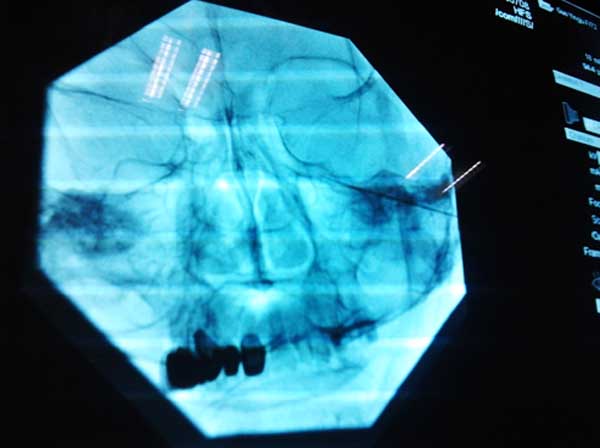

在确定了坚叔的诊断后,首先给予了药物治疗,服用镇痛药物加巴喷丁等近一个星期,疼痛可以部分缓解,但仍不能完全缓解,为进一步解决疼痛,后在介入室成功实施右侧三叉神经射频热凝联合化学毁损术。微创手术治疗后,患者术后右侧面部疼痛消失,术后1周内未出现预期中的脸部肿胀、显著麻木感、咬肌无力等严重并发症。出院一周后门诊随访,患者诉未再服止痛药,终于可以正常吃饭、洗脸了,患者及家属对治疗效果均非常满意。

微创手术中定位照片